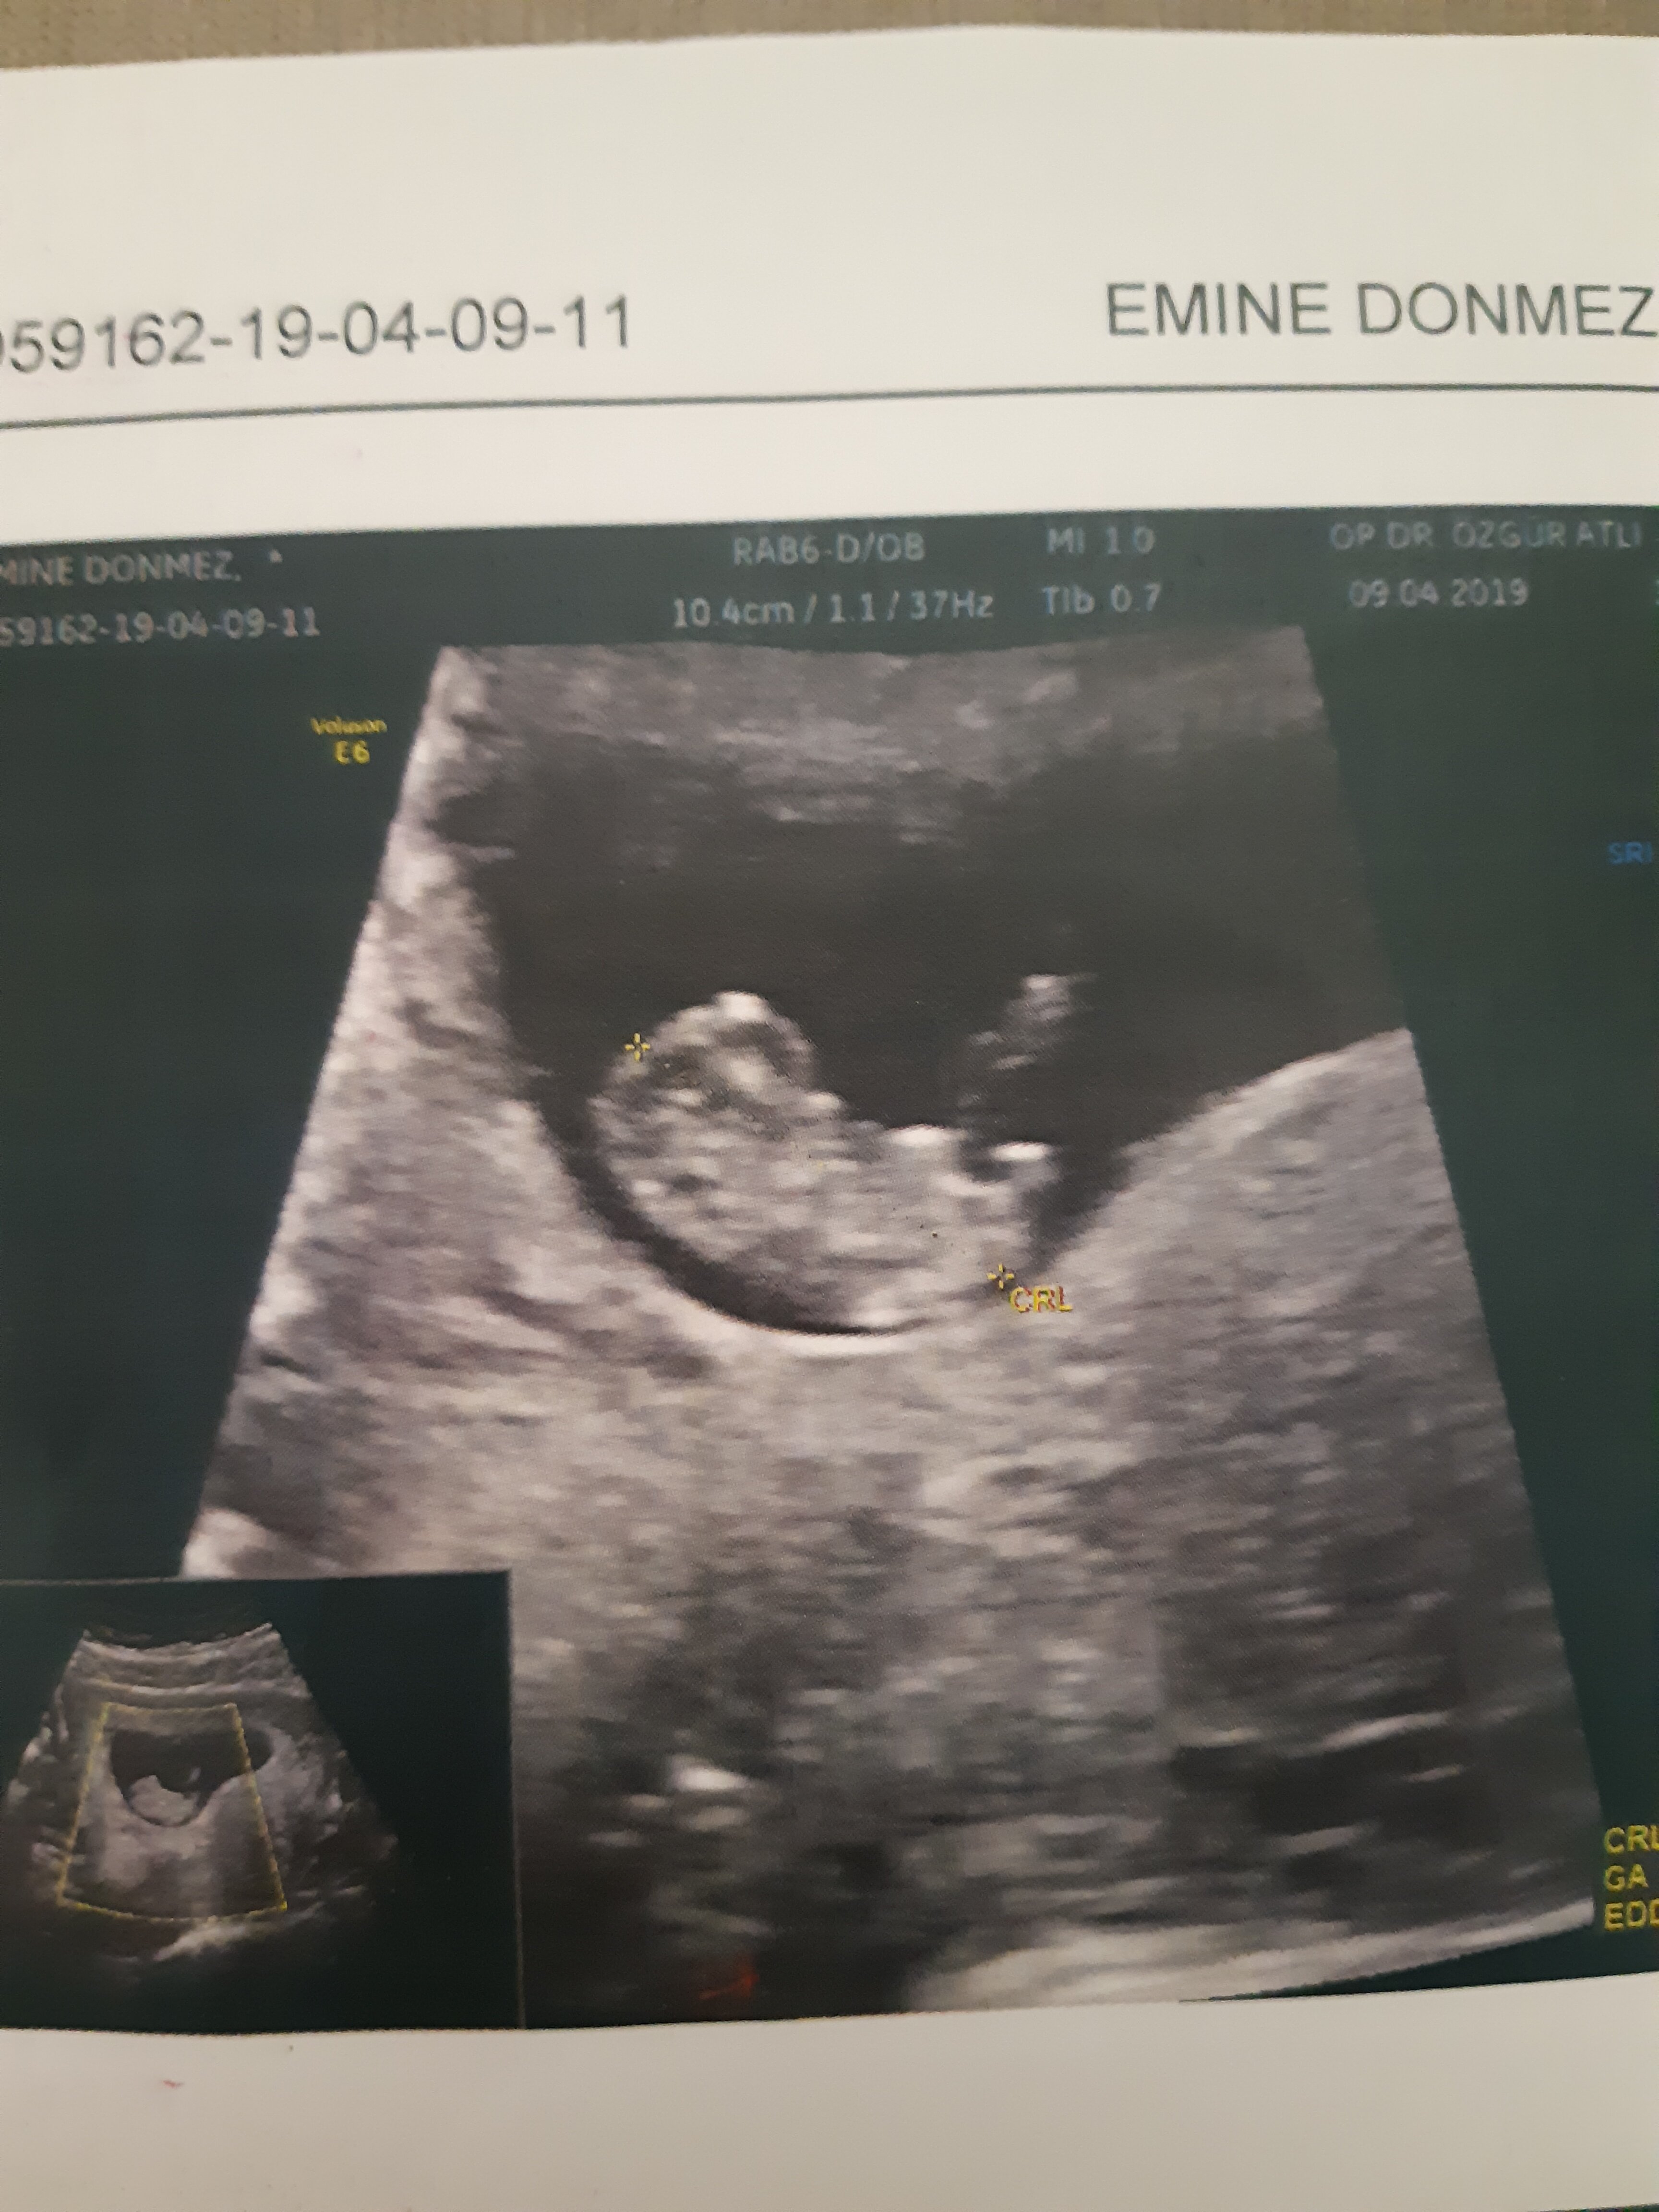

Benm kendi doktorum olmadğı içn 12. hftada farklı bir doktora ikili test yaptrmştm ve cinsiyetinin kız olduğunu söylemşti

ama 16. haftada tekrar gittiğimde kendi doktorum erkek olduğunu söyledi sizce nedir? doğru sonuç için detaylıyı mı beklemeliyim???

Belittiğiniz haftalarda cinsiyet tahmininde yanılmalar olabilir. Gebeliğin 17-18-20 . haftalarında bebeğinizin cinsiyetini net olarak öğrenebilirsiniz.